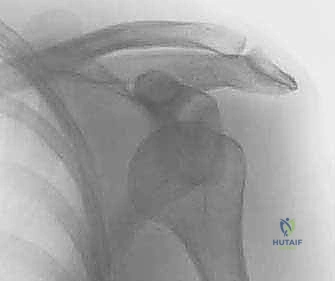

- التصوير بالأشعة السينية (X-rays): لاستبعاد وجود كسور عظمية مصاحبة للخلع، مثل كسر هيل-ساكس (Hill-Sachs Lesion) وهو انبعاج في رأس عظم العضد.

- التصوير بالرنين المغناطيسي (MRI / MR Arthrogram): المعيار الذهبي لتشخيص الأنسجة الرخوة. يوضح هذا التصوير بدقة متناهية حجم تمزق الشفا الحقاني (آفة بانكارت)، حالة الأربطة، ودرجة ترهل محفظة المفصل.